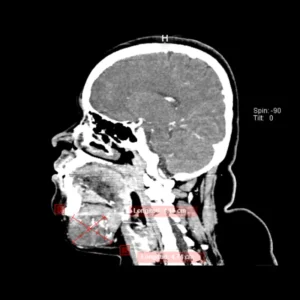

Tumores Óseos

Malformaciones vasculares hemangionas

El diagnóstico y el tratamiento de las malformaciones arteriovenosas requieren un amplio conocimiento de esta rara enfermedad.

Son alteraciones congénitas del desarrollo vascular causando lesiones identificables de la piel mucosa y tejidos blandos, generalmente benignos, sus presentaciones clínicas varían conforme a la extensión y localización.

Lesiones en la lengua